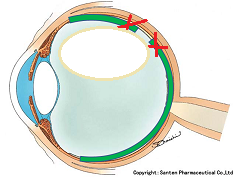

黒目(角膜)から入ってきた光は、目の奥の方のフィルム(網膜)に当たります。網膜は一つの束(視神経)になって、最終的には脳ミソにつながり、「物が見える」という事になります。

図の赤矢印の部分は視神経乳頭と言って、網膜が集まって束になる部分なのですが、実はこの部位のみ光を感じ取ることはできないのです。

写真だと水色の部分が視神経乳頭(マ盲点)になります。ちなみに、物を見る中心部の網膜は黄斑と呼ばれ、オレンジの矢印に当たります。

マリオット盲点以外の部位が欠ける場合は病気となるのですが、視野が欠ける代表的な疾患として、緑内障があります(日本人の失明の原因の第一位)。